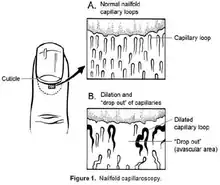

For assessment of the morphological and functional aspects of microcirculation, nailfold videocapillaroscopy (NVC) can be used, in which videocapillaroscopy is performed at the nailfold, where capillaries are arranged with the longitudinal axis parallel to the skin surface, so that they can be examined along their entire length.[8]

NVC has been largely used not only for investigating peripheral microangiopathy, but also as a sort of “window” to systemic microvascular dysfunction. Although its main application is within the connective tissue diseases such as systemic scleroderma and dermatomyositis, it has been employed in non-rheumatic diseases with microvascular involvement such as diabetes mellitus, essential hypertension and COVID-19 infection.[8]